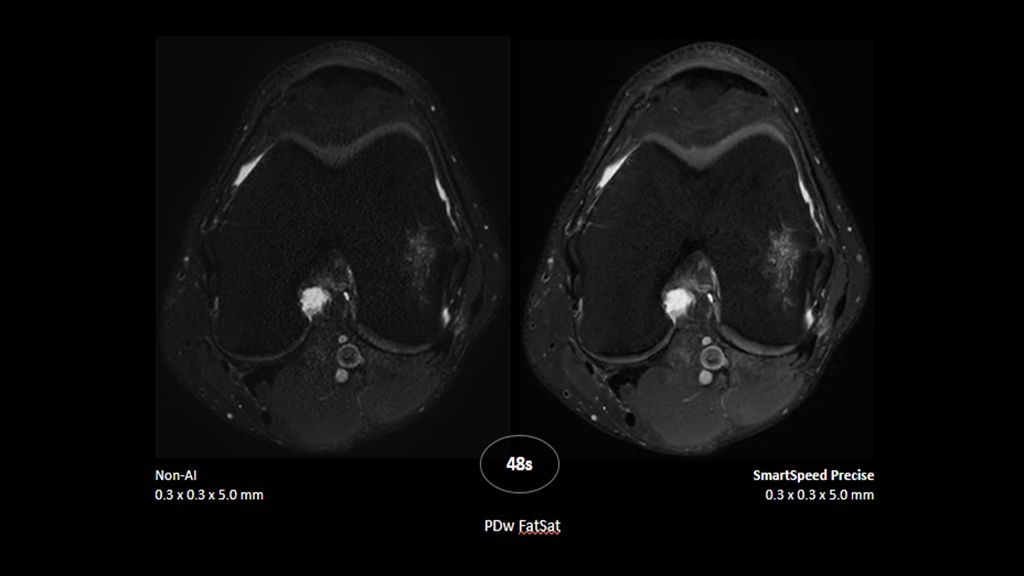

2. Reconstruction technology Compared to conventional (SENSE/ Compressed SENSE, SmartSpeed AI) imaging. Sharpness was evaluated with phantom scanning.